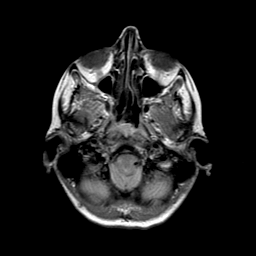

Metastatic bronchogenic carcinoma: proton density-weighted MR -- Slice #2

[Home][Help][Clinical] Slice 2